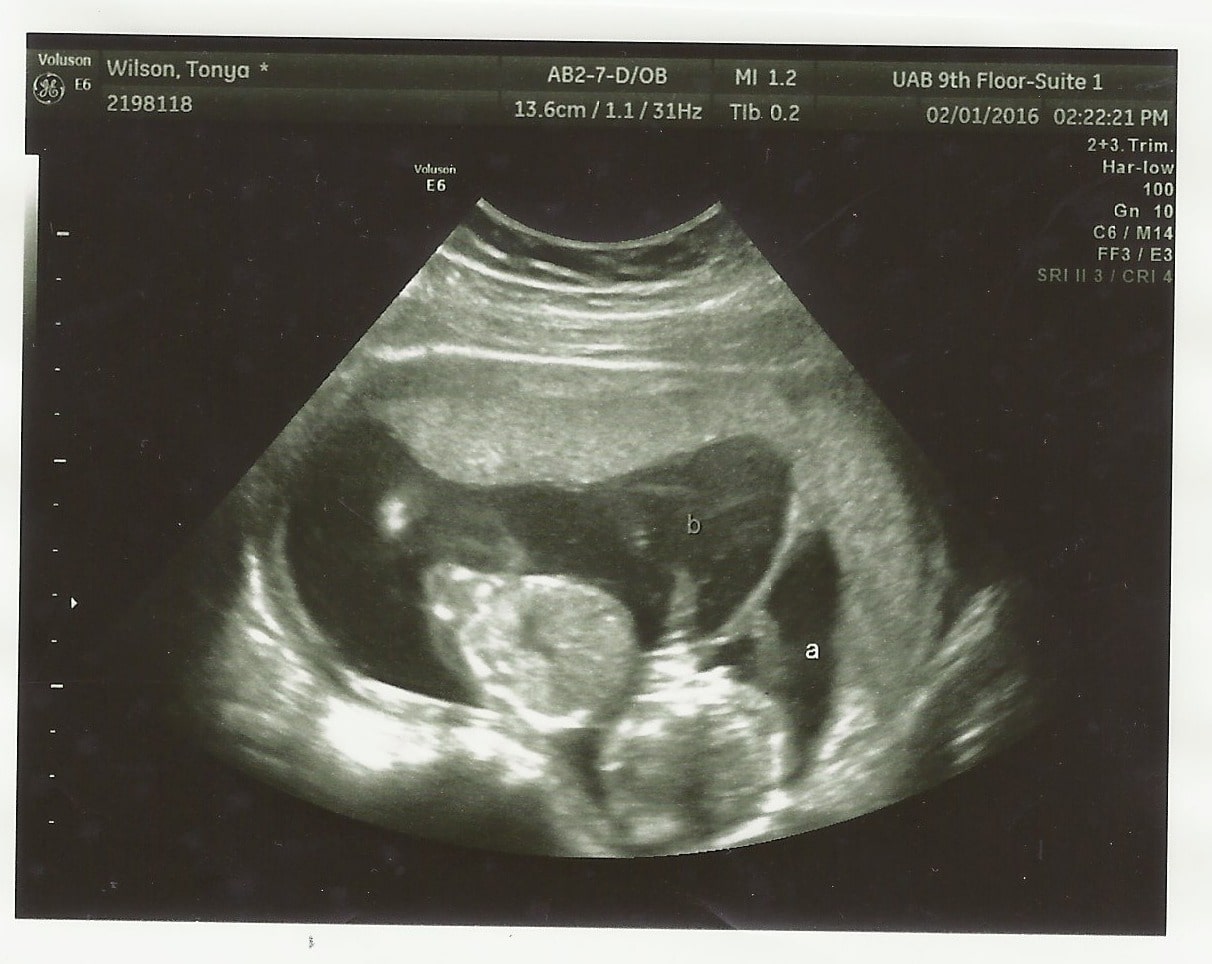

Ultrasound Photos at 15 Weeks Pregnant With Twins

Your twins’ eyelids are fused shut, but they can sense light. Ultrasounds done this week may reveal your twins’ genders, but don’t be surprised if it’s still too early to tell.